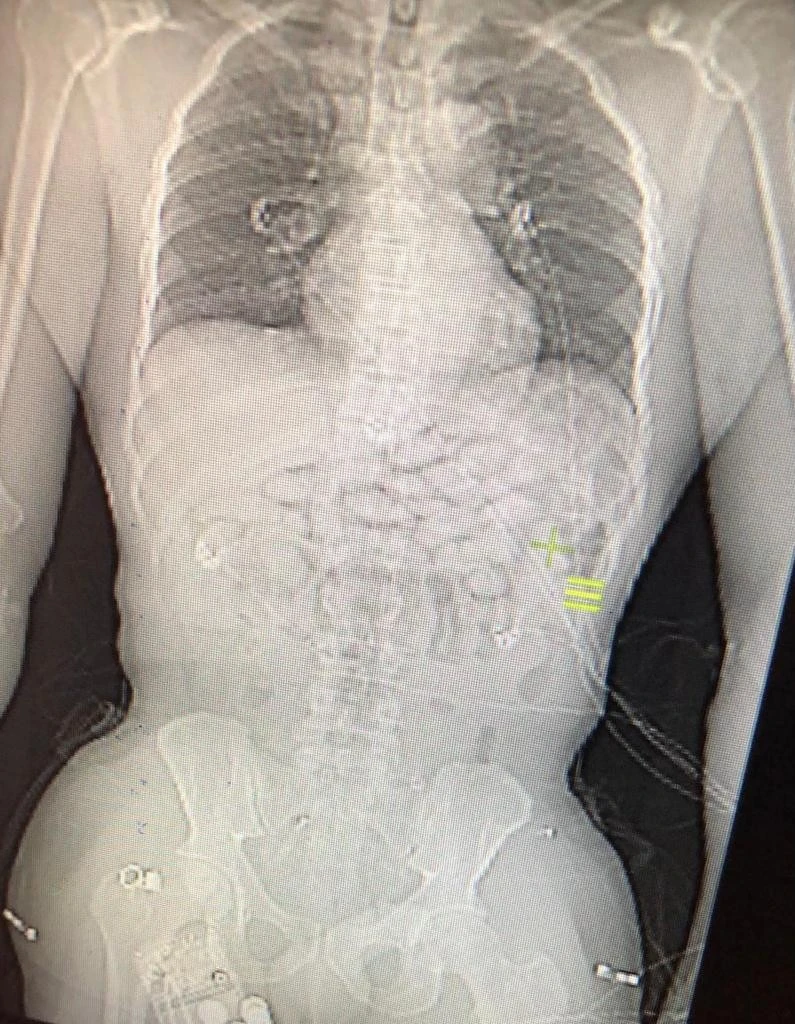

Afrika ülkesi Benin' den geçtiğimiz 29 Aralık'ta İstanbul Havalimanı'nı aktarmalı olarak İspanya'nın Madrid şehrine giden Gana uyruklu bir yolcu, Dış Hatlar Transit Alanda, emniyet güçlerinin risk analizi çalışmalarında şüpheli olarak görüldü. Uyuşturucu kuryeliği yaptığı şüphesiyle gözaltına alınan şahsın hastanede çekilen röntgen kontrollerinde midesinde 93 kapsül metamfetamin diye tabir edilen uyuşturucu madde olduğu tespit edildi. Gözaltına alınan şahıs emniyetteki işlemlerinin ardından adliyeye sevk edildi.